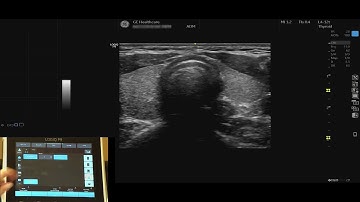

LOGIQ P9 Tutorials: Getting Started